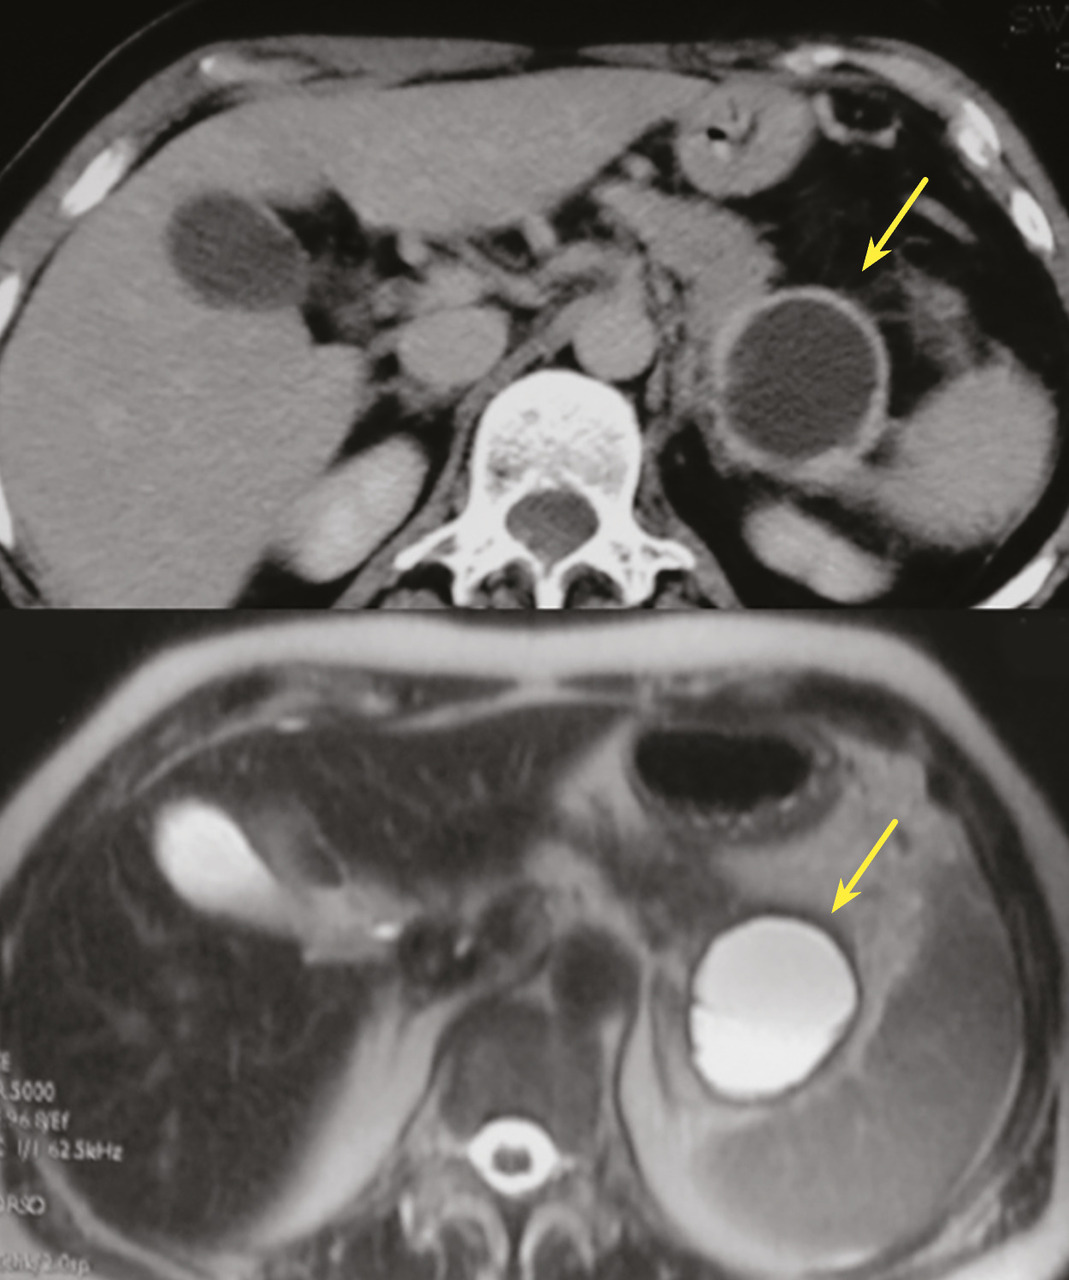

Tumeur kystique mucineuse

Les tumeurs kystiques mucineuses (TKM) sont des lésions précancéreuses bordées par un revêtement épithélial, sécrétant de la mucine. Il est caractéristique de trouver un stroma de type ovarien, positif en immunohistochimie à la progestérone. Le sex-ratio est fortement en faveur des femmes  : (20 femmes pour 1 homme). La découverte est principalement fortuite ou plus rarement sur pancréatite aiguë. Il s’agit d’une lésion unique, macrokystique, sans communication avec les canaux pancréatiques. Elle se situe quasi exclusivement au niveau de la face postérieure du corps et de la queue du pancréas (fig. 3). La lésion est uni- ou multiloculaire, limitée, hypodense, avec rehaussement de la paroi. Il existe de possibles nodules muraux, calcifications périphériques ou cloisons internes.

Le taux de risque d’évolution vers un cancer est inconnu. Les critères comme une taille supérieure à 7 cm, une épaisseur des septas et de la paroi supérieure à 3 mm, un nombre de kystes supérieur à quatre, la présence de nodules, un contenu liquidien hyperintense en séquences IRM T1, une compression ou infiltration périlésionnelle sont associés à des critères de dégénérescence en cystadénocarcinome.11

Dans les recommandations européennes, les experts proposent (à l’instar des TIPMP) une surveillance si la taille de la lésion est inférieure à 40 mm, en cas d’absence de nodules et si le patient est asymptomatique. Pour les lésions de 30 à 40 mm, il est recommandé de prendre en compte l’âge et les comorbidités. Les modalités de surveillance sont la réalisation d’une IRM ou d’une écho-endoscopie tous les six mois pendant un an puis tous les ans. En cas de résection, celle-ci doit être la plus limitée possible, en privilégiant la chirurgie d’épargne de type énucléation ou pancréatectomie médiane. Le risque de récidive postopératoire est nul, il n’est pas recommandé de suivi spécifique si la résection était complète.